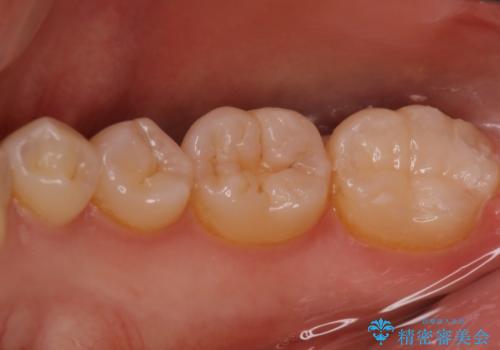

- 他院にて虫歯を指摘され、セカンドオピニオンを希望し当院へ来院されました。以前より磨きずらさと舌感の悪さは自覚していたそうです。清掃性、機能性に優れたセラミックインレーにて治療をすることとなりました。

レントゲンから昔詰めた保険の詰め物が入っていることが確認できました。詰め物と歯の隙間が虫歯になっていたためしっかり取り除き、適合の良いセラミックインレーを入れました。